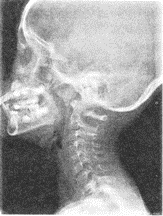

3.患者男性,5岁,反复呛咳,张口呼吸,有鼾声,鼻腔分泌物多。X线检查如图所见,最可能的诊断是

正确答案:D 解题思路:鼻咽腺样体为位于鼻咽顶部的一团淋巴结组织,儿童期可呈生理性肥大,5岁左右最明显,以后逐渐萎缩,至15岁左右达成人状态。临床上常见鼻塞、张口呼吸,入睡时有鼾声。X线鼻咽侧位片,见鼻咽顶后壁软组织广泛肿胀、增厚,表面柔软光滑,鼻咽腔因腺样体占位而狭小,局部骨质无改变。